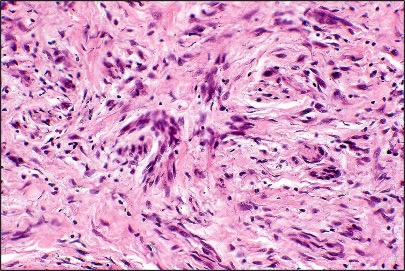

•Paucicellular spindle cell infiltrate with “myxoid” fine to a dense collagenous stroma

•Hyperchromatic nuclei

•Variable pleomorphism

•Lymphoid aggregates*